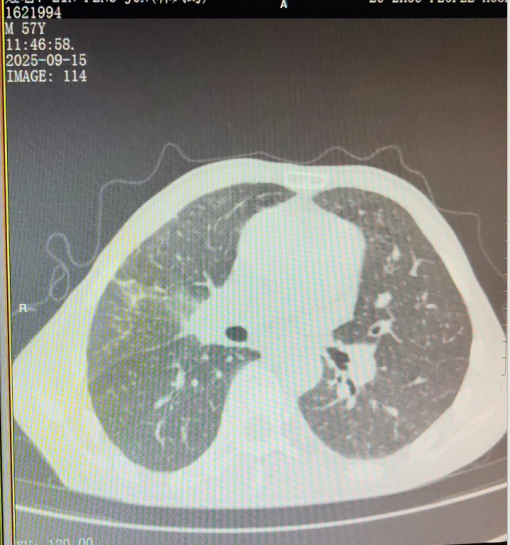

诊断结果确实严峻:右肺中叶鳞状细胞癌晚期,肿瘤已侵犯心包,并转移至双肺、纵隔多处淋巴结。

希望,就在这份坚持中悄然生长。完成六个疗程的化疗后,检查结果令人振奋:CT显示肿瘤病灶明显退缩,左肺转移灶消失。

曾经困扰他的咳嗽、胸闷等症状消失了,体重回升了二十多斤,身体状况显著改善。